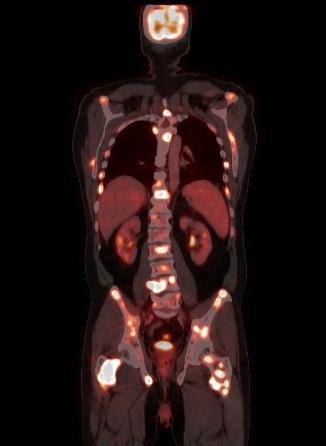

FDG PET/CT appears to be more sensitive (85%) than skeletal survey for the detection of small lytic bone lesions.

Leukemia. 2009 • Diagnosis is confirmed with bone marrow demonstrating greater than 10% involvement by malignant plasma cells with either CRAB or SLiM Malignant Plasma cells seen on biopsy AND ≥1 “CRAB” feature OR have >1 SLiM ‘high risk” features: C: Calcium elevation (>11 mg/dL) R: Renal- low kidney function; (serum creatinine >2 mg/dL) A: Anemia –low red blood count (Hb <10 g/dL) B: Bone disease (≥1 lytic lesions on skeletal radiography, CT, or PET-CT) S: >60% Plasma Cells on Bone Marrow biopsy Li: Serum light chain ratio >100 M: >1 lytic lesions on MRI (or PET/ CT scan)